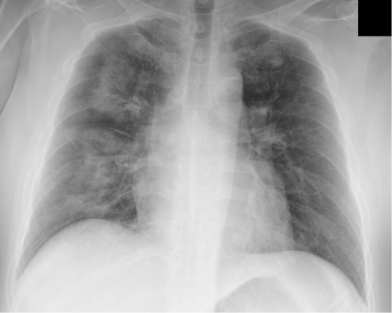

白细胞计数9.830/Mm³(轻度升高);初始高敏肌钙蛋白T(Hs-TnT)0.013ng/ml(正常),4小时后升至0.044ng/ml(未达第99百分位值0.52ng/Ml);初始N末端脑利钠肽前体(Nt-ProBNP)49pg/ml(正常),次日升至 137pg/ml。心电图(ECG):窦性心动过速,无明显St-T改变(图1)。超声心动图(入院时):左心室无扩大,室间隔厚度8mm,左心室后壁厚度9mm,舒张末期直径45mm,收缩末期直径30mm,左心室射血分数(EF)62%,室壁运动正常。胸片及胸部CT:均提示肺淤血(图2、图3)。心肌闪烁显像(入院第5天):201 - 铊显像示左心室中度灌注缺损,123I-Bmipp 显像示左心室前壁、下壁摄取严重减少,提示灌注-代谢不匹配(图4)。超声心动图(入院第5天):EF 56%,E/e' 12.3,中隔 e' 5.2cm/s,三尖瓣反流速度 2.9m/s,左心房容积指数 25ml/m²。

(图2)